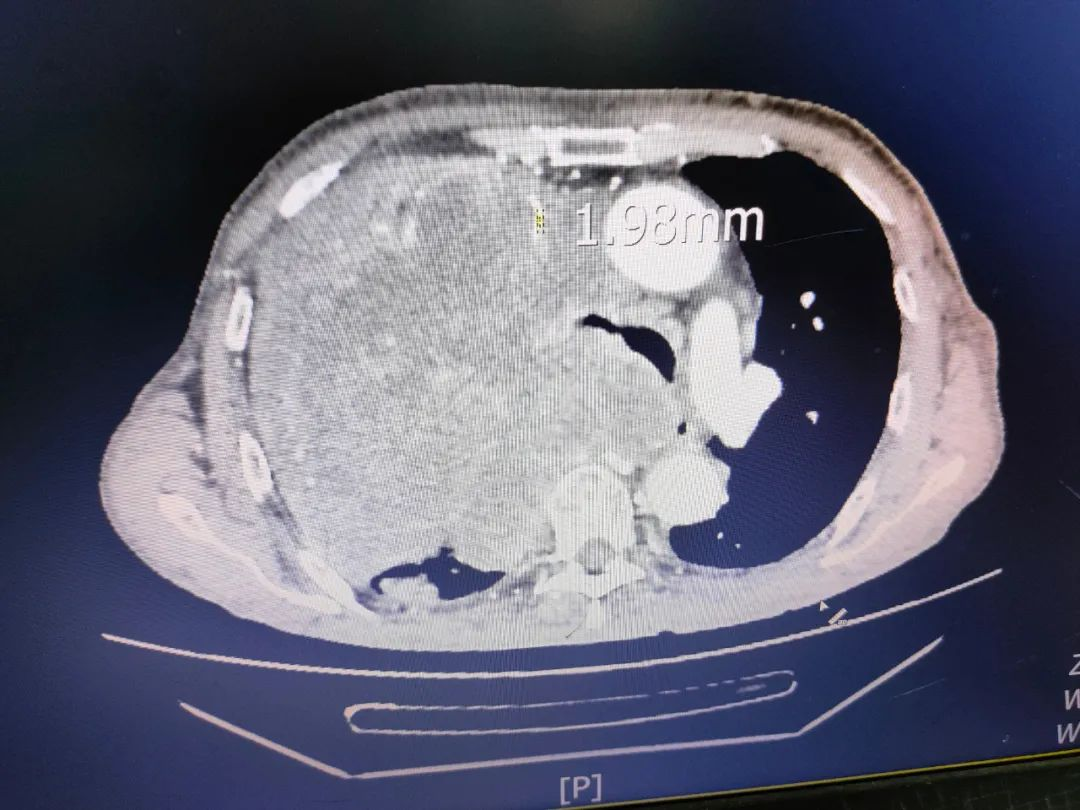

病例介绍:患者胡某某,诊断右肺上叶中央型肺癌并多发转移。确定治疗方案后,呼吸与危重症医学科学科带头人罗少华主任首先想到的就是让静疗专家会诊,为患者选择安全的静疗通路。李柳英副主任了解了患者病情,查看CT片,左上肺肿瘤的大小为152mm×141mm×167mm(前后×左右×上下径),最大直径占满左胸腔,上腔静脉严重压迫,上腔静脉最小管径1.99mm,患者出现上腔静脉压迫综合征,上腔静脉压迫综合征是上肢PICC置管、输液的绝对禁忌症,经与管床医生充分讨论后,决定经患者下肢置入PICC进行治疗。